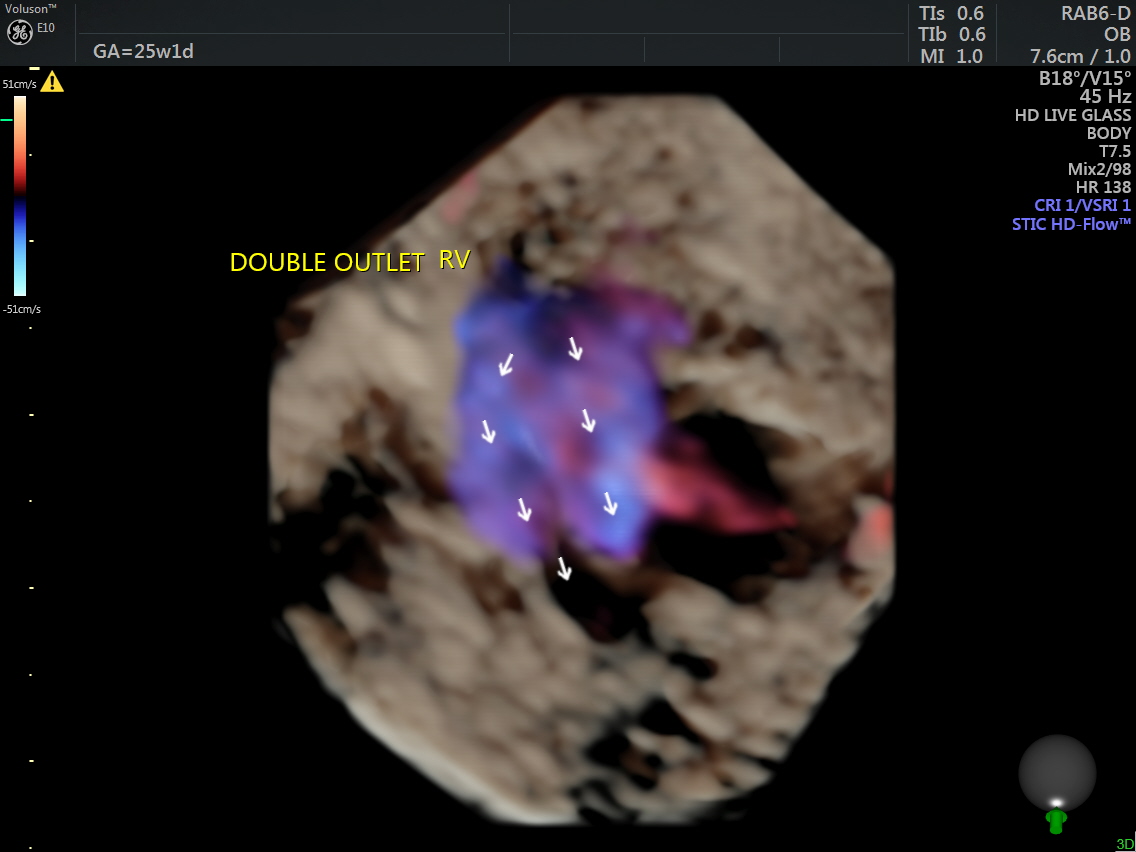

This was a 25-year-old primi referred for a 2nd opinion for Double Outlet Right Ventricle. No VSD was detected by the sonologist.

The following are some reconstructions.

This fetus showed left heart dysplasia, a small VSD and Double Outlet Right Ventricle with malposition of the great arteries.